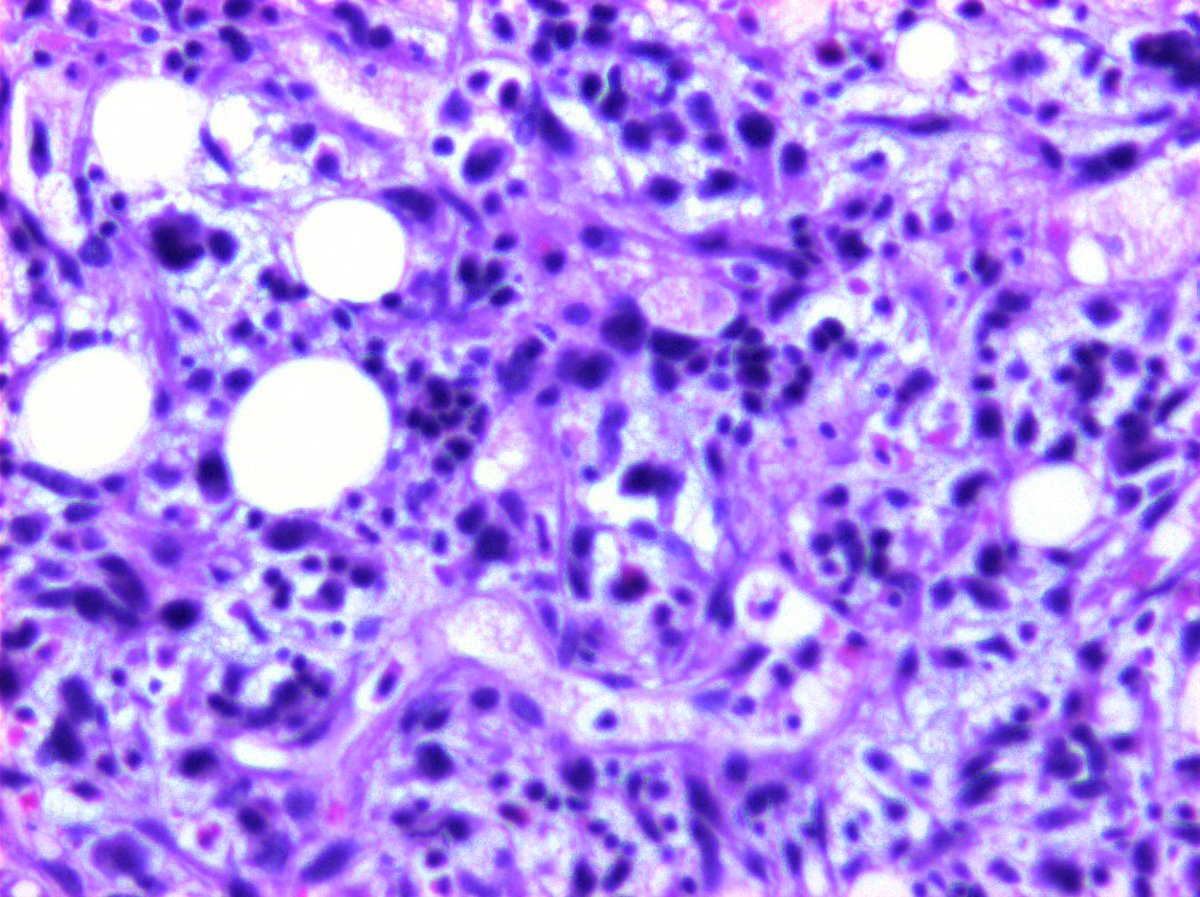

@KukMariya Myelolipomas are clonal. I published this a million years ago.

Hey Pathology twitter! Thoughts?